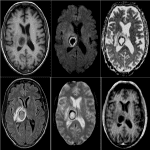

Ở những bệnh nhân AIDS thì nhiễm Toxoplasma là hiện tượng nhiễm trùng cơ hội quan trọng nhất ở hệ thần kinh trung ương. Người ta cho rằng những người mắc bệnh AIDS thì hơn 95% các trường hợp viêm não do Toxoplasma là do tái nhiễm ký sinh trùng. 23% bệnh nhân AIDS tử vong do nhiễm Toxoplasma…